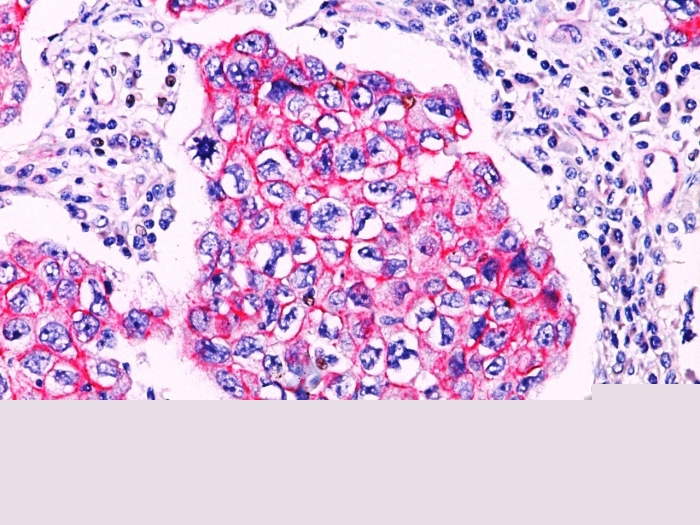

Formalin-fixed, paraffin-embedded breast lobular carcinoma stained with Catenin, beta PAb. Note cytoplasmic staining in lobular carcinoma.

Beta-catenin associates with the cytoplasmic portion of E-cadherin, which is necessary for the function of E-cadherin as an adhesion molecule. In normal tissues, beta-catenin is localized to the membrane of epithelial cells, consistent with its role in the cell adhesion complex. In breast ductal neoplasia, beta-catenin is usually localized in cellular membranes. However, in lobular neoplasia, a marked redistribution of beta-catenin throughout the cytoplasm results in a diffuse cytoplasmic pattern. Immuno-staining of beta-catenin and E-cadherin is helps in the accurate identification of ductal and lobular neoplasms, including a distinction between low-grade ductal carcinoma in situ (DCIS) and lobular carcinoma. Additionally, some rectal and gastric adenocarcinomas demonstrate diffuse cytoplasmic beta-catenin staining and a lack of membranous staining, mimicking the staining pattern observed with lobular breast carcinomas.